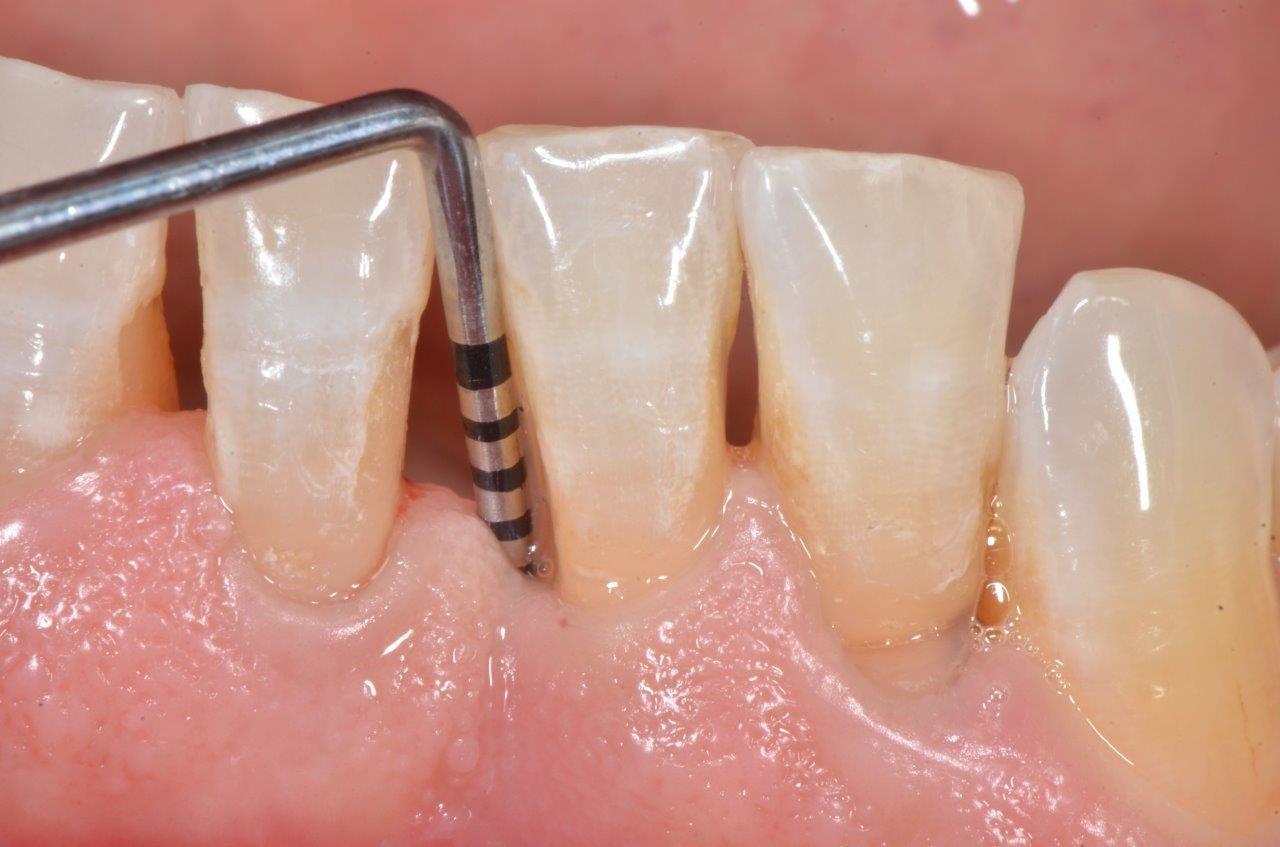

Pocket irrigation is a dental procedure to remove all the dirt residing between the teeth and the gum line. The harmful bacteria are prevented from replicating and you can save your teeth. The treatment is also used to deliver antimicrobials under your gum line.

Pocket irrigation is advised for several oral problems. The tool used is known as a pocket irrigator.

- Interdental cleaning is one of the major reasons for pocket irrigation. The irrigator breaks plaque and bacteria present between your teeth. The pockets stay shallow and the gum tissues stay healthier.

- They also aid in subgingival cleanings without damaging the tissues under your gum line.